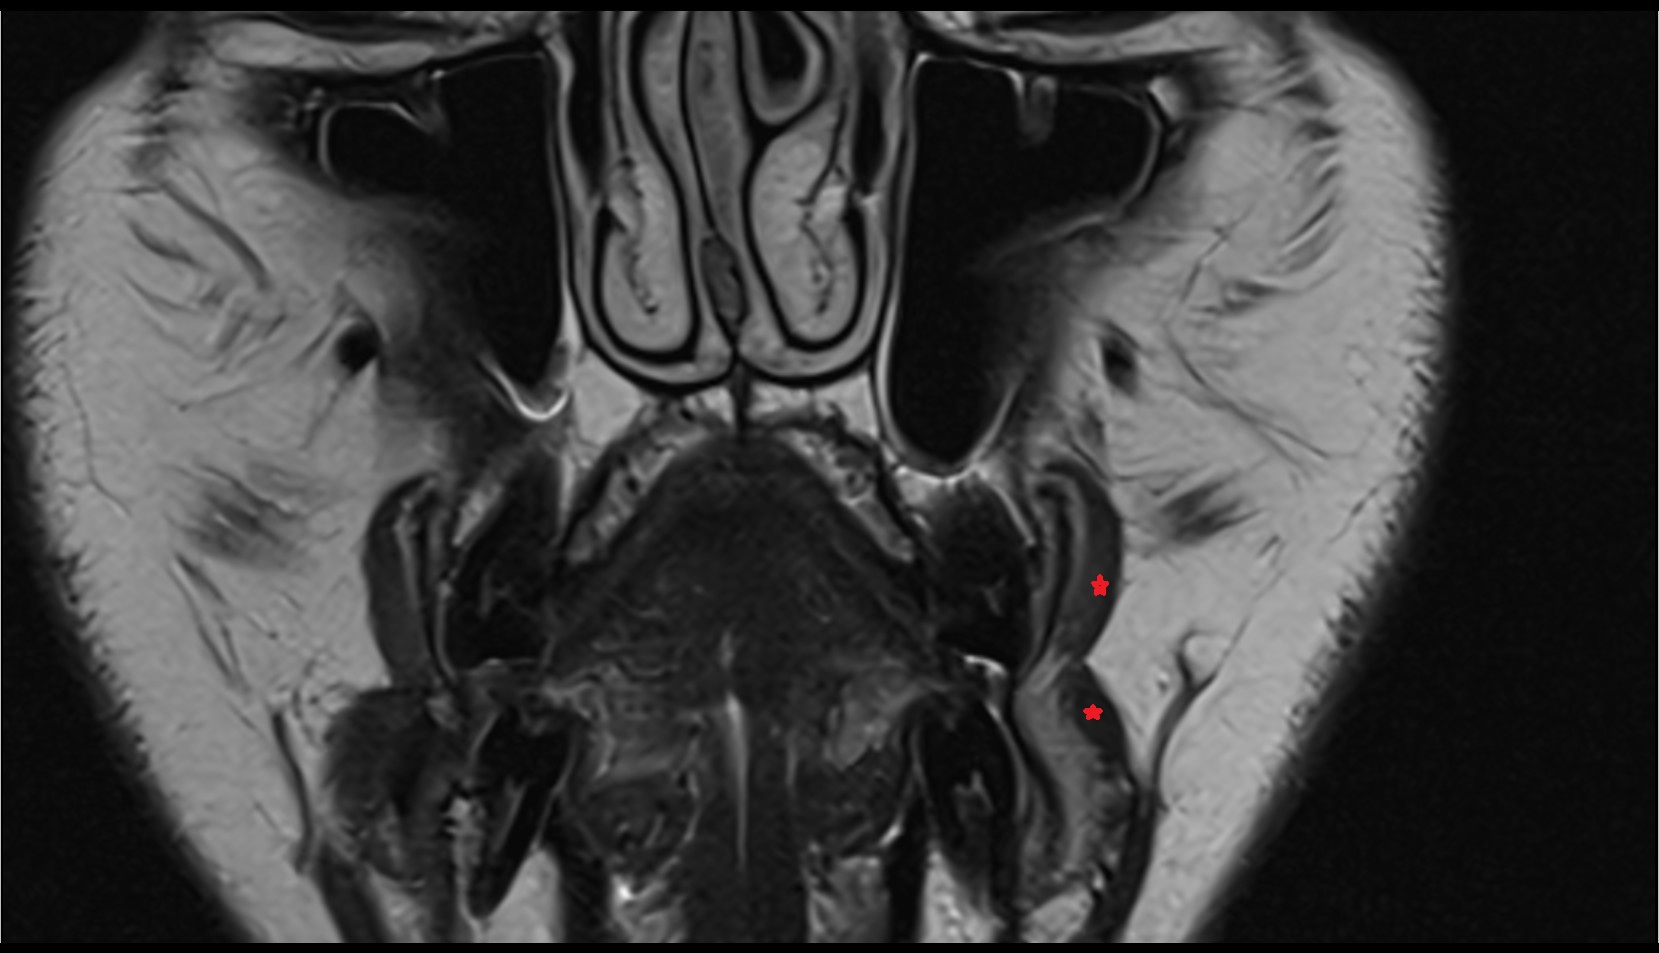

- Temporomandibular joint

- Mandibular condyle

- Mandibular fossa

- Articular disc of temporomandibular joint

- Intermediate zone of articular disc

- Superior retrodiscal layer